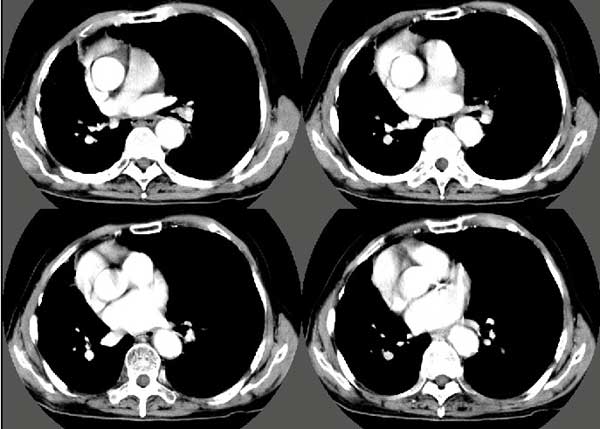

以下是引用扬仪在2005-5-12 20:46:40的发言:[br]右肺呈术后改变;双侧肺野散在分布斑片状、点状高密度病灶,(似可见“树芽征”);左上尖后段见斑团状高密度病灶(2个层面?),边缘毛糙,段性分布,与斜裂相邻,临近胸膜粘连;增强示病灶边缘强化,内呈水样密度;心影、纵隔右移,内可见4r淋巴结肿大。[br]意见:1、双肺继发性肺结核,左上为干酪病灶;[br] 2、矽肺合并感染;[br] 3、建议抗痨+抗炎。 [br]愚人之见,请高人指教!